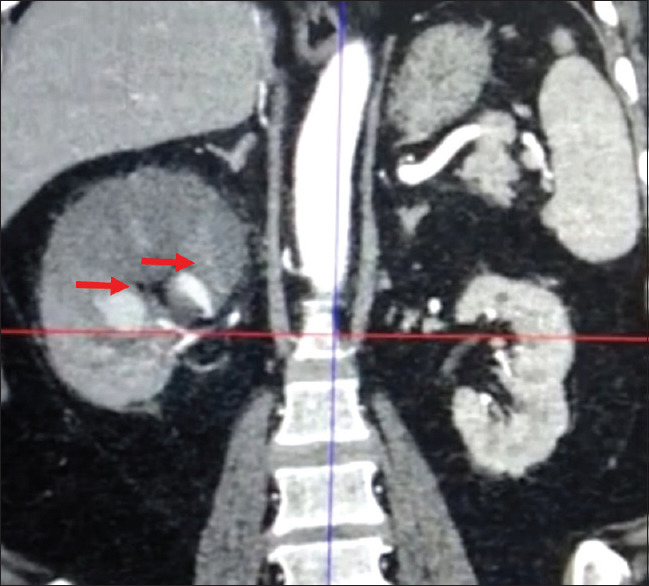

本病例报告讨论了 COVID-19 康复后出现的一种罕见的严重并发症--导致右肾动脉假性动脉瘤的肾粘液瘤病。一名曾接受过 COVID-19 治疗的 59 岁患者出现干咳、侧腹疼痛和血尿。他被诊断为肾动脉假性动脉瘤伴肾粘液瘤病。成功的治疗包括紧急血管栓塞术、全身用脂质体两性霉素 B 以及稳定后的根治性肾切除术。该病例强调了COVID-19后警惕性随访的重要性,尤其是对接受类固醇治疗的患者,并强调了采用多学科方法及时诊断和有效治疗粘液瘤病相关并发症的必要性。

This case report discusses a rare and severe complication of COVID-19 recovery - renal mucormycosis leading to right renal artery pseudoaneurysm. A 59-year-old patient, previously treated for COVID-19, presented with dry cough, flank pain, and hematuria. He was diagnosed with renal artery pseudoaneurysm with renal mucormycosis. Successful management included urgent angioembolization, systemic liposomal amphotericin B, and subsequent radical nephrectomy post-stabilization. The case underscores the importance of vigilant post-COVID-19 follow-up, particularly in patients treated with steroids, and highlights the need for a multidisciplinary approach for timely diagnosis and effective management of mucormycosis related complications.